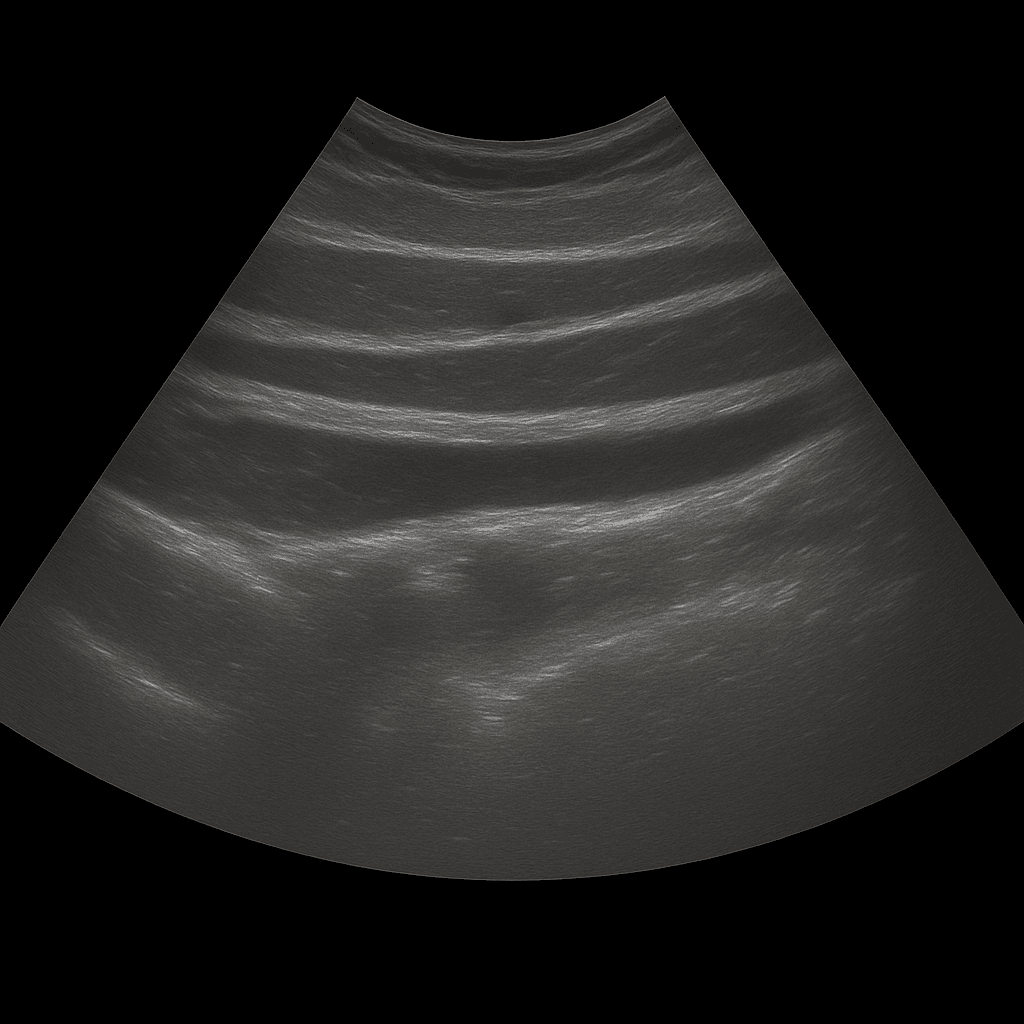

An abdominal ultrasound is used to examine the skin, subcutaneous tissue and muscles of the abdominal wall. The examination is performed by a specialist in radiology and provides detailed images in real time that can show changes that cause pain, swelling or visible bulges in the abdomen. Abdominal ultrasound is often used when there is suspicion of hernia, fluid accumulation, hematoma or other changes in the soft tissues.

Unlike MRI and CT, which are used to map deeper organs and structures in the abdominal cavity, ultrasound is the first choice for examining superficial changes in the abdominal wall. Ultrasound shows muscles, tissue layers and possible defects in real time - without radiation or contrast media.

The examination is performed while you lie on your back. A gel is applied to the skin and the doctor moves the ultrasound probe over the area where you are experiencing discomfort. The abdominal wall is examined in different planes, both at rest and under slight tension, which makes it possible to see any hernias or defects that appear when the abdomen is loaded.